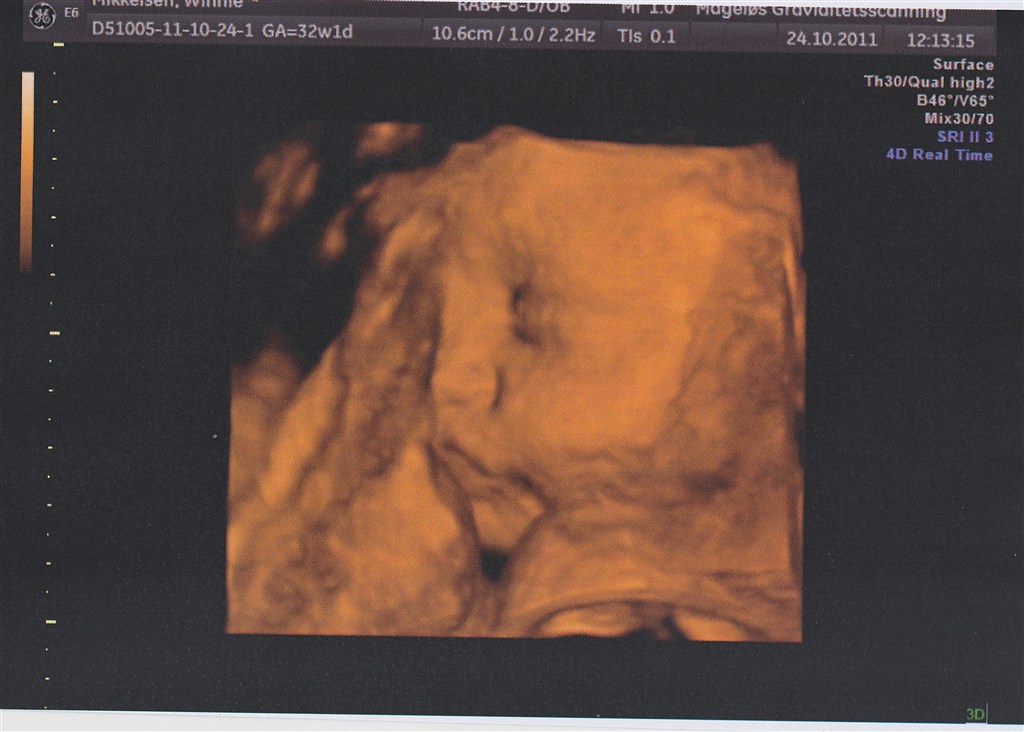

Selve 3D-scanningen gik dog lidt mere besværligt. Min moderkage ligger fortil (dog heldigvis højt), og lillepigen lå med hovedet vendt ind imod den. Jeg drak koldt vand og hoppede lidt, men det hjalp ikke meget.

Da jeg kom tilbage havde hun vendt hovedet lidt - stadig ikke ideelt men nok til at vi kunne få lidt billeder halvt i profil.

Det var sjovt at se det lille ansigt med den lille nedadvendte mund (præcis som min storesøsters datter har) og de lange øjenvipper. Det vigtigste var dog at hun havde det godt derinde og at vi fik bekræftet at alt var ok

Vedhæftede fotos (klik for at se i fuld størrelse)